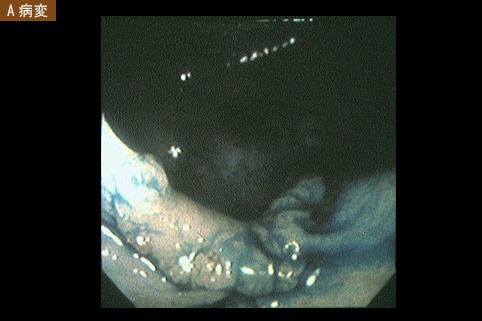

Criteria of Hist.ClassificationMalignant epithelial tumor/Adenocarcinoma

LocationLarge intestine(Colon)/Transverse colon

Technique, MethodEndoscopy

Macroscopic TypesType 0/IIa (IIa+IIc) Superficial elevated and depressed type

Size15 - 19

Depth of Tumor Invasionsubmucosa